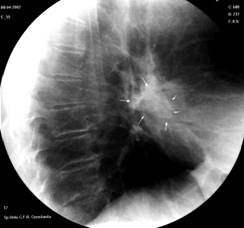

3. Bronsiectazia – reprezinta dilatatia anormala, permanenta, a uneia sau mai multor bronhii mijlocii si mici datorita distrugerii tesutului musculo-elastic al peretelui bronhic, asociata de obicei cu bronsita cronica.

Fig. 22 – Bronsiectazii bazale (bronhografie stanga)

Boala bronsiectatica difuza antreneaza pe radiografia standard o ingrosare a desenului bronsic, sau imagini areolare, mai mult sau mai putin intinse ce pot realiza aspectul de plaman “in fagure”.

Bronsiectaziile localizate se manifesta sub forma unor pneumopatii recidivante. In ambele cazuri diagnosticul de certitudine este apanajul bronhografiei care precizeaza sediul, intinderea si aspectul leziunilor.